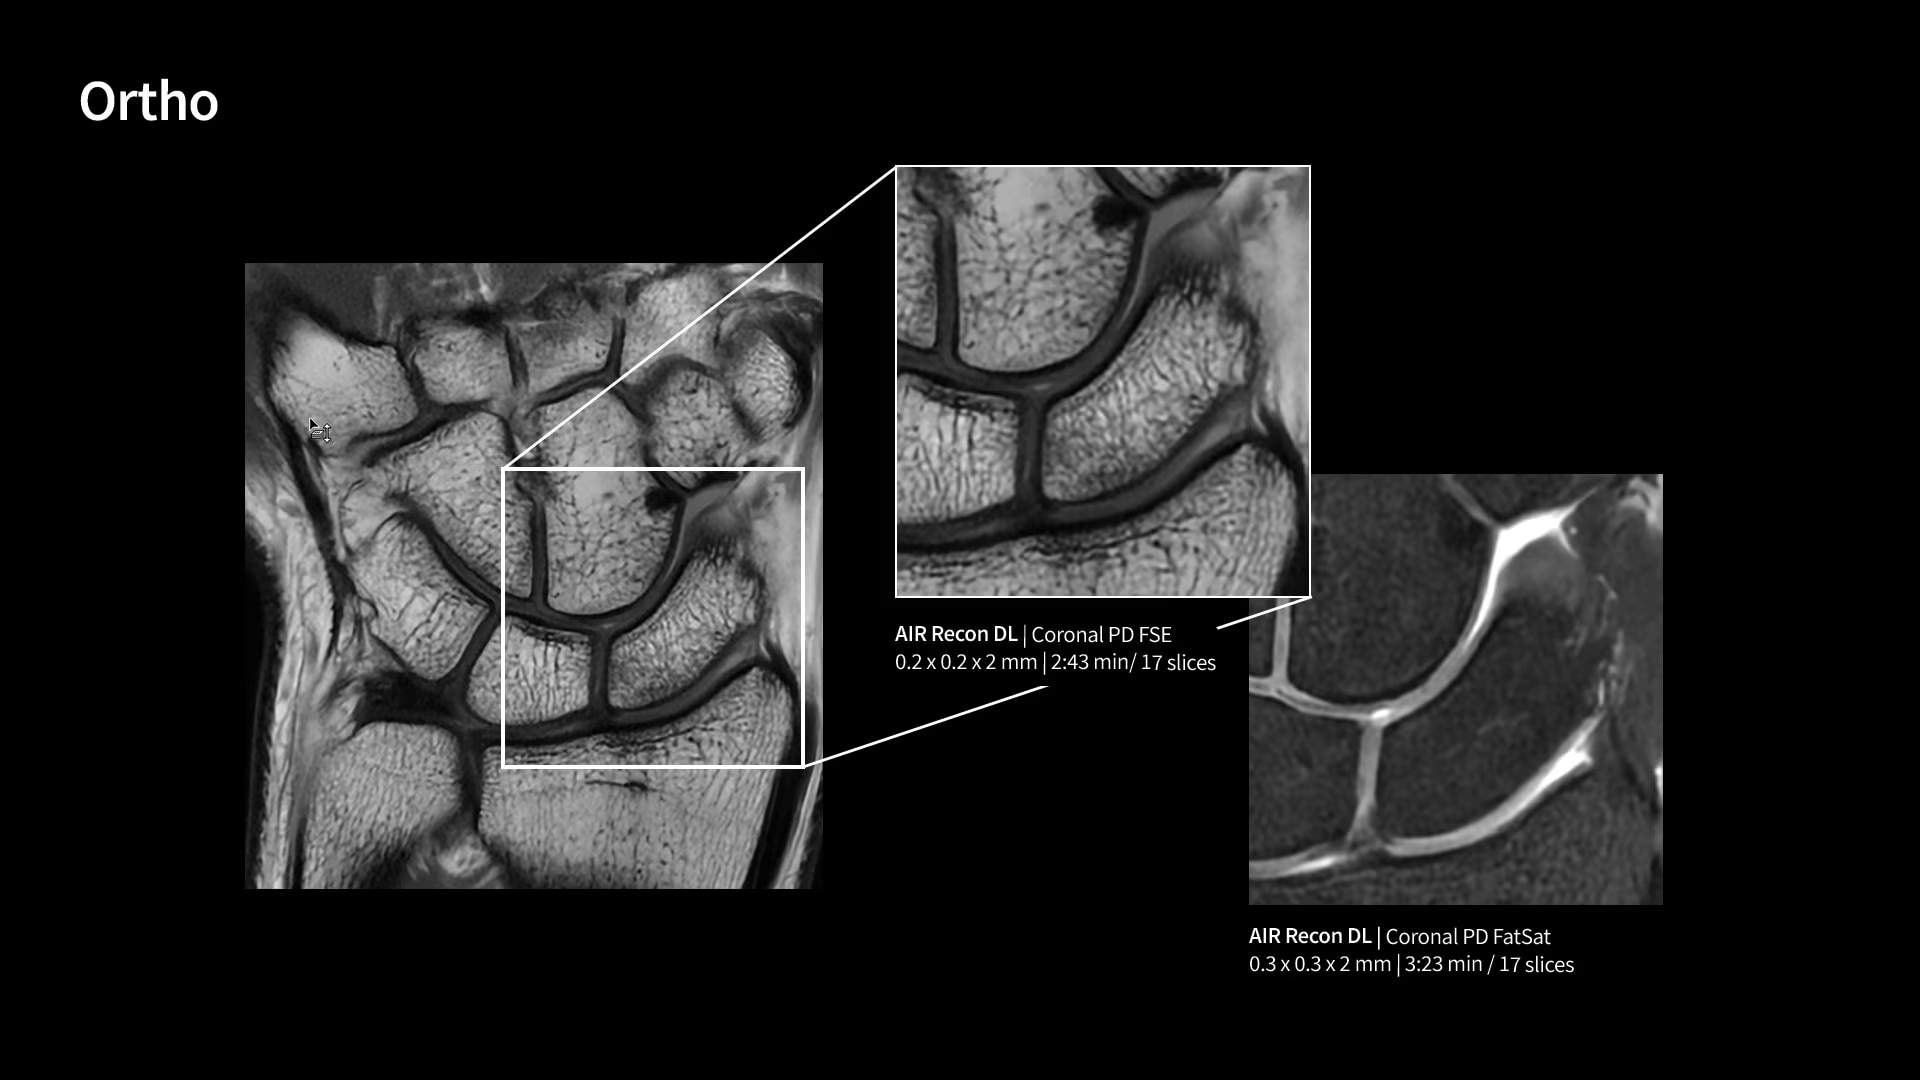

Within cardiovascular diseases, the functional assessment of the heart is an essential imaging application. SIGNA Sprint is powered by built-in AI technologies—Sonic DL™, AIR Recon DL and AIR x™—enabling high-quality imaging even in the most demanding anatomies.

With GE HealthCare's comprehensive suite of deep-learning solutions integrated into SIGNA Sprint, you can unlock the full potential of your MRI system. No need for complicated patient setups or imaging protocols. The exceptional intelligence of our AI solutions offer multiple benefits, with AIR Recon DL giving pin-sharp images, Sonic DL accelerating scans up to 12x, and AIR x enabling automated slice placement. All helping to enhance your department’s workflow efficiency, increase patient throughput, and get the diagnostic clarity you need, faster.¹ Meaning you can spend more time on what truly matters—personalized patient care, enabling optimized treatment plans and treatment response monitoring—ultimately, supporting better clinical outcomes.